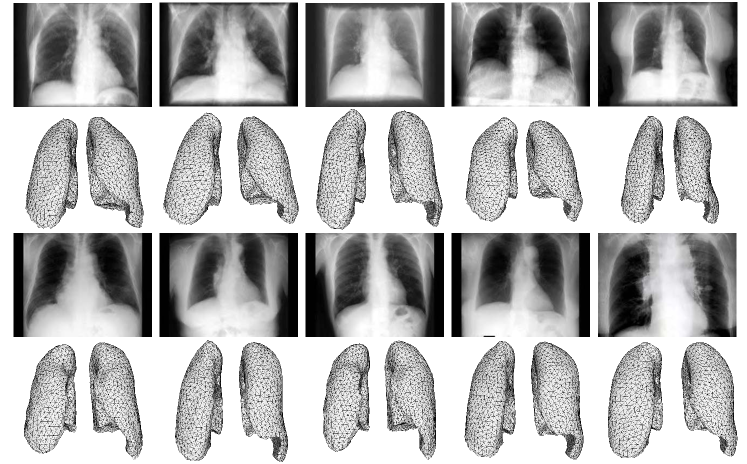

4.1 3D Lung Shape Reconstruction from Synthetic Images

Fig. 4 shows the reconstruction results of 3D lungs with different shapes based on the synthetic data. Our network is capable of dealing with drastic variations (even though the real-world medical scenarios are far less challenging). For each input image, our network is able to pick the template which most resembles the ground truth model within the corresponding branches, and predict the accurate spatial arrangement between left and right lungs to generate the final high-fidelity 3D lung shape pairs. The reconstruction error (HD on mesh) is mapped into a unified colormap range and it shows that the reconstruction results are pretty good qualitatively and quantitatively.

Refer to caption

Figure 4: Qualitative reconstruction and visualization results of some lung shapes with drastic variations. The reconstruction error (HD on mesh) is mapped into a unified colormap range (hotter colors indicate larger errors and colder colors indicate smaller errors) and the mesh resolution increases from top to bottom (e.g., 1K, 2.5K, 5K, 10K vertices).